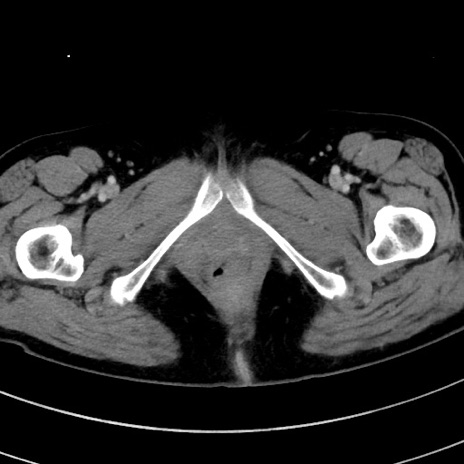

症例9(横断像)

【症例】 60歳代女性

【主訴】むかつき、みぞおちの痛み

【現病歴】3日前よりむかつきがあり、食事がとれない。

【既往歴】糖尿病

【身体所見】発熱なし、心窩部圧痛軽度あるも、腹膜刺激症状なし。

【データ】WBC 7400、CRP 1.92